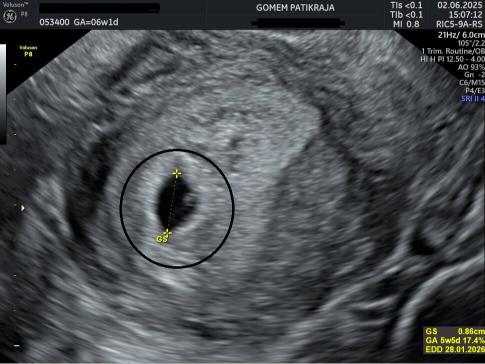

Gambaran Hasil USG Janin 6 Minggu

Minggu ke-6 adalah tahap penting karena jantung janin biasanya sudah mulai berdetak. Kepala terlihat lebih besar dibanding tubuh karena otak berkembang cepat. Tangan dan kaki mulai terbentuk walaupun masih kecil. Ibu sering mengalami mual di pagi hari, mudah lelah, dan perubahan suasana hati. Istirahat cukup dan makan sedikit tapi sering bisa membantu mengurangi keluhan. Pemeriksaan USG pada minggu ini biasanya sudah bisa melihat denyut jantung.

Pada minggu ke-6 biasanya detak jantung janin sudah mulai terbentuk dan sering sudah bisa terlihat saat pemeriksaan USG, walaupun pada sebagian kehamilan bisa terlihat sedikit lebih lambat.